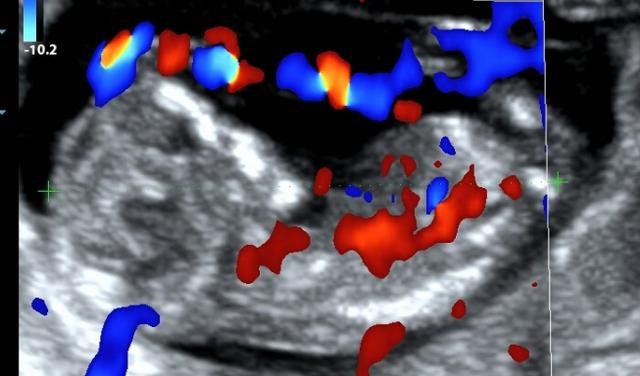

3个月,也就是约12周。

此时胎动已经开始活跃了,只是孕妈妈可能还感受不到。但在超声下却可以看到TA很活泼哟。

其实早在约6周的时候就可以看到宝宝有节律的心跳了。

除了心跳,我们还能看见TA的整个身体雏形了。